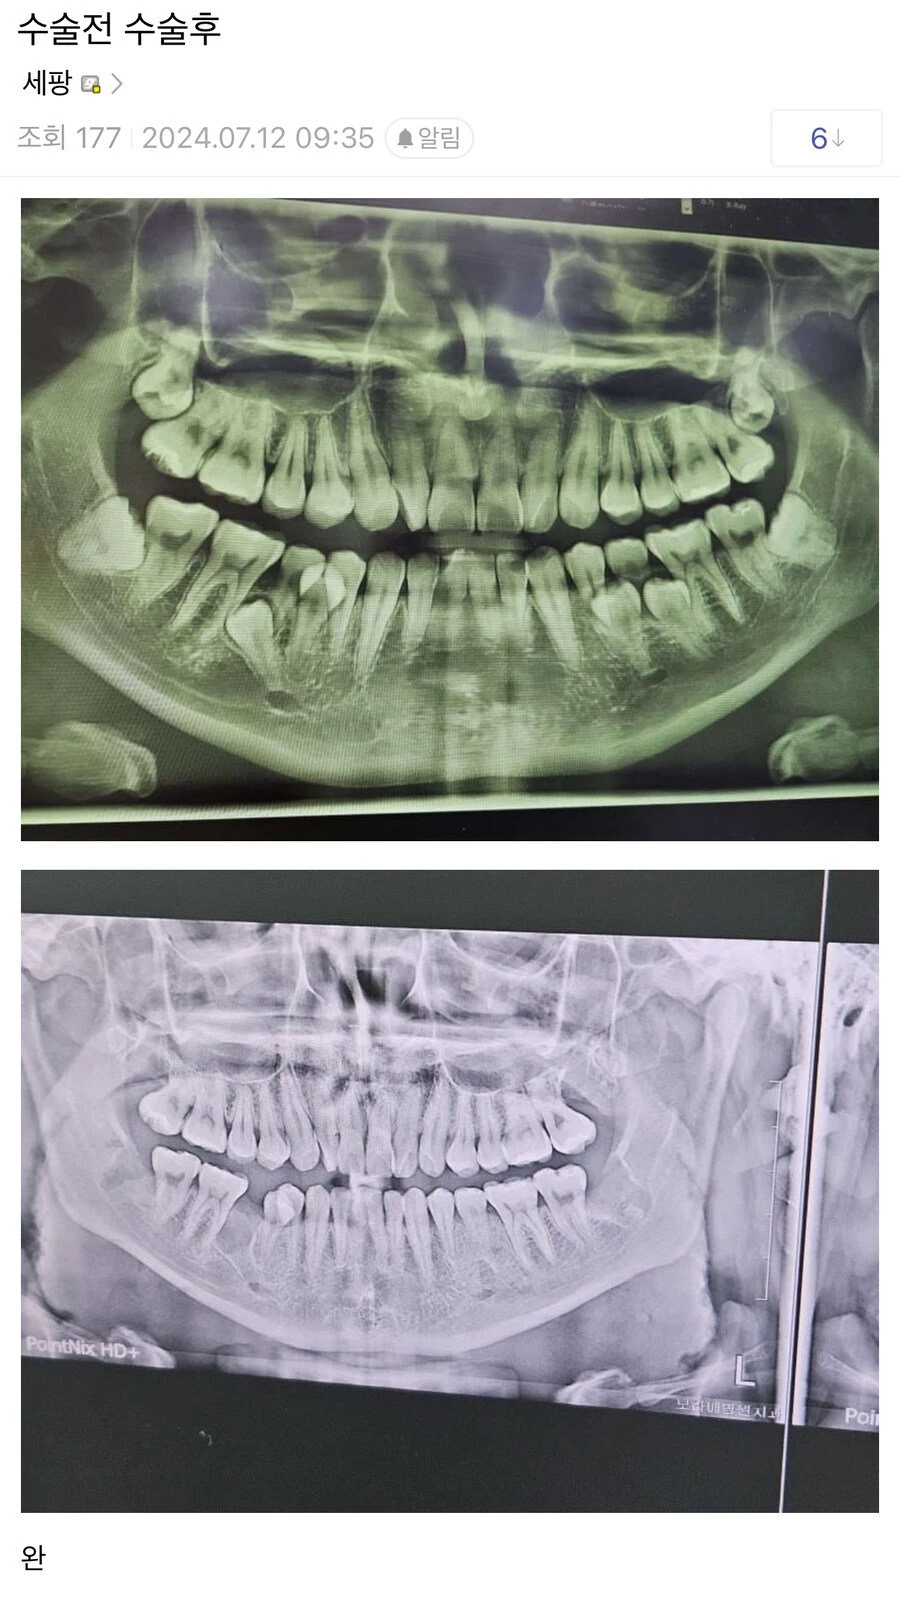

유명했던 사랑니 레전드 수술 결과 나옴.jpg